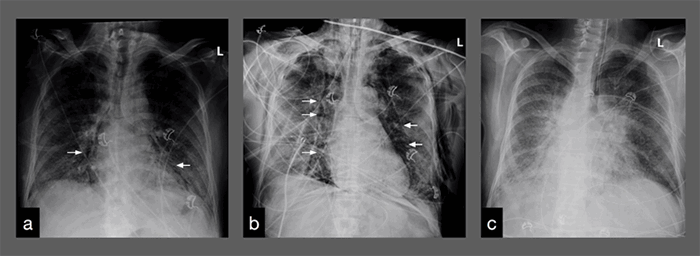

After the first of three days of prone positioning while intubated, the chest X ray demonstrated near complete resolution of the bilateral pneumothoraces with improvement of the previously noted pneumomediastinum. By the third day of prone positioning, both the pneumomediastinum and pneumothoraces had resolved radiographically and prone positioning was terminated (Figure 2). This was not an intended consequence of prone positioning and has not been noted previously in the literature.

Figure 2. X-ray imaging demonstrating trace pneumomediastinum pre-intubation on hospital day 15. A) Pneumomediastinum with biapical pneumothoraces after intubation the same day. B) Post-prone positioning resolution of pneumomediastinum and pneumothoraces of pneumomediastinum. C) Pneumothoraces on hospital day 18.